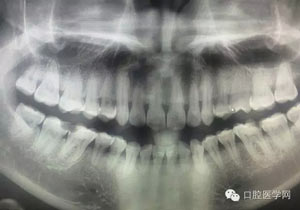

做出高質量的根管治療,是我們做根管的醫生所追求的,我們知道沒有百分百的事情,但是我們一直在追求,希望盡我們的最大努力去保留患者的牙齒。成功率的提高,首先需要我們去選擇病例,有保留價值的我們去做,沒有保留價值的我們盡早拔除,免得炎癥范圍的擴大,造成更多骨量的流失。還有就是對咬合以及患者咬合習慣的改變,嚴重的影響到關節的問題。我們在選擇病例的時候尤其是老年人,我們還是多問幾句,血壓怎么樣,是否過高,如若過高會影響我們麻醉藥品的選擇;肝功怎么樣,影響我們麻醉劑量的選擇;心功能怎么樣,是否有瓣膜病變,是否有做手術,術后有無回訪,有否遵照醫囑一直服用藥物,心臟是否有瓣膜感染。我們治療前是否需要預防口服消炎藥物,說道消炎藥物,我們給患者別隨便開口服藥物,我們要事先了解好藥物的性能、特點、適應癥,哪些人可以用,哪些不可以用,現在的法規規定阿莫西林口服要做皮試,我們沒有事情做的時候,還是多看下常用藥的說明書,看清楚其上面的適應癥及禁忌癥,別拿著以前的知識來指導現在的臨床。做老年同志的病例,要十分的小心,根管本身就有難度,我們還要分出一些時間關注患者的表情的變化,是否有不適,如若出現不適,我們需要做出相應的措施,以改善患者的不適。別祖傳秘方專治駝背,駝背好了,人出現了問題了。

做根管的,都想做些難度大一點的,彎曲根管了、斷針了,可是臨床上很多時候是中等及以下難度的居多,我們要做的是盡我們所能做好這一部分,將我們力所能及的做好,而不是不切實際的幻想做一些我們條件設備不夠的病例。有些時候看到一些病例,很難想象是我們同行做的,我們是人,而不是神,我們也需要生活,我們追求效益沒有錯,我們給患者推薦好的材料,最終受益多的還是患者,這沒有錯,但是我們不是賣產品的,我們的本質是醫療,不是流水線上的工人,將商品加工賣出去,我們所做的一切都是建立在符合修復設計原則的基礎上的,如若不符合,我們做的再美觀,再便宜,那又有什么意義呢?無論我們做什么樣子的修復體或者是治療,我們的標準是一致的,教科書上有明確的規定,我們這社會也有畸形,就拿簡單的冠修復來說,我們花費的精力是差不多的,我們需要的步驟是一樣的,但是價格差別那么大,是我們自己制定價格的問題,還是社會的問題?如若我們的冠的價格的制定差別不大,我們將更多的心思放到醫療本身上面,那么最終受益的還是患者,可是現在是顛倒的,我們成了產品的推銷者,整天想著怎么樣將價格高的冠賣給患者,而忽略了提高學習我們自身專業能力,我們整天想著怎么樣將環境打造的多么的好,然而材料上面卻是怎么樣的省怎么來,什么便宜用什么,裝修上面我們可以花很多,材料我們卻很摳,有時候我們材料買很好,可是我們卻束之高閣,很多時候我們講理念,講概念,可是我們卻很少腳踏實地的去做我們的專業,只是用這些新鮮的名詞去和患者溝通。給大家看幾張不良的修復設計。